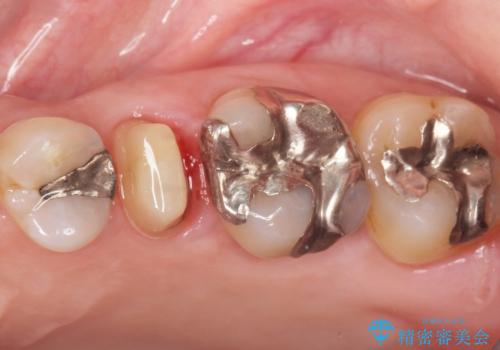

- 歯の根のあたりの歯ぐきを押すと痛むことを主訴に来院された患者様です。

精査したところ、左上の小臼歯(左上5)の神経が死んでいました。

根管治療後、セラミッククラウンによる補綴を行いました。